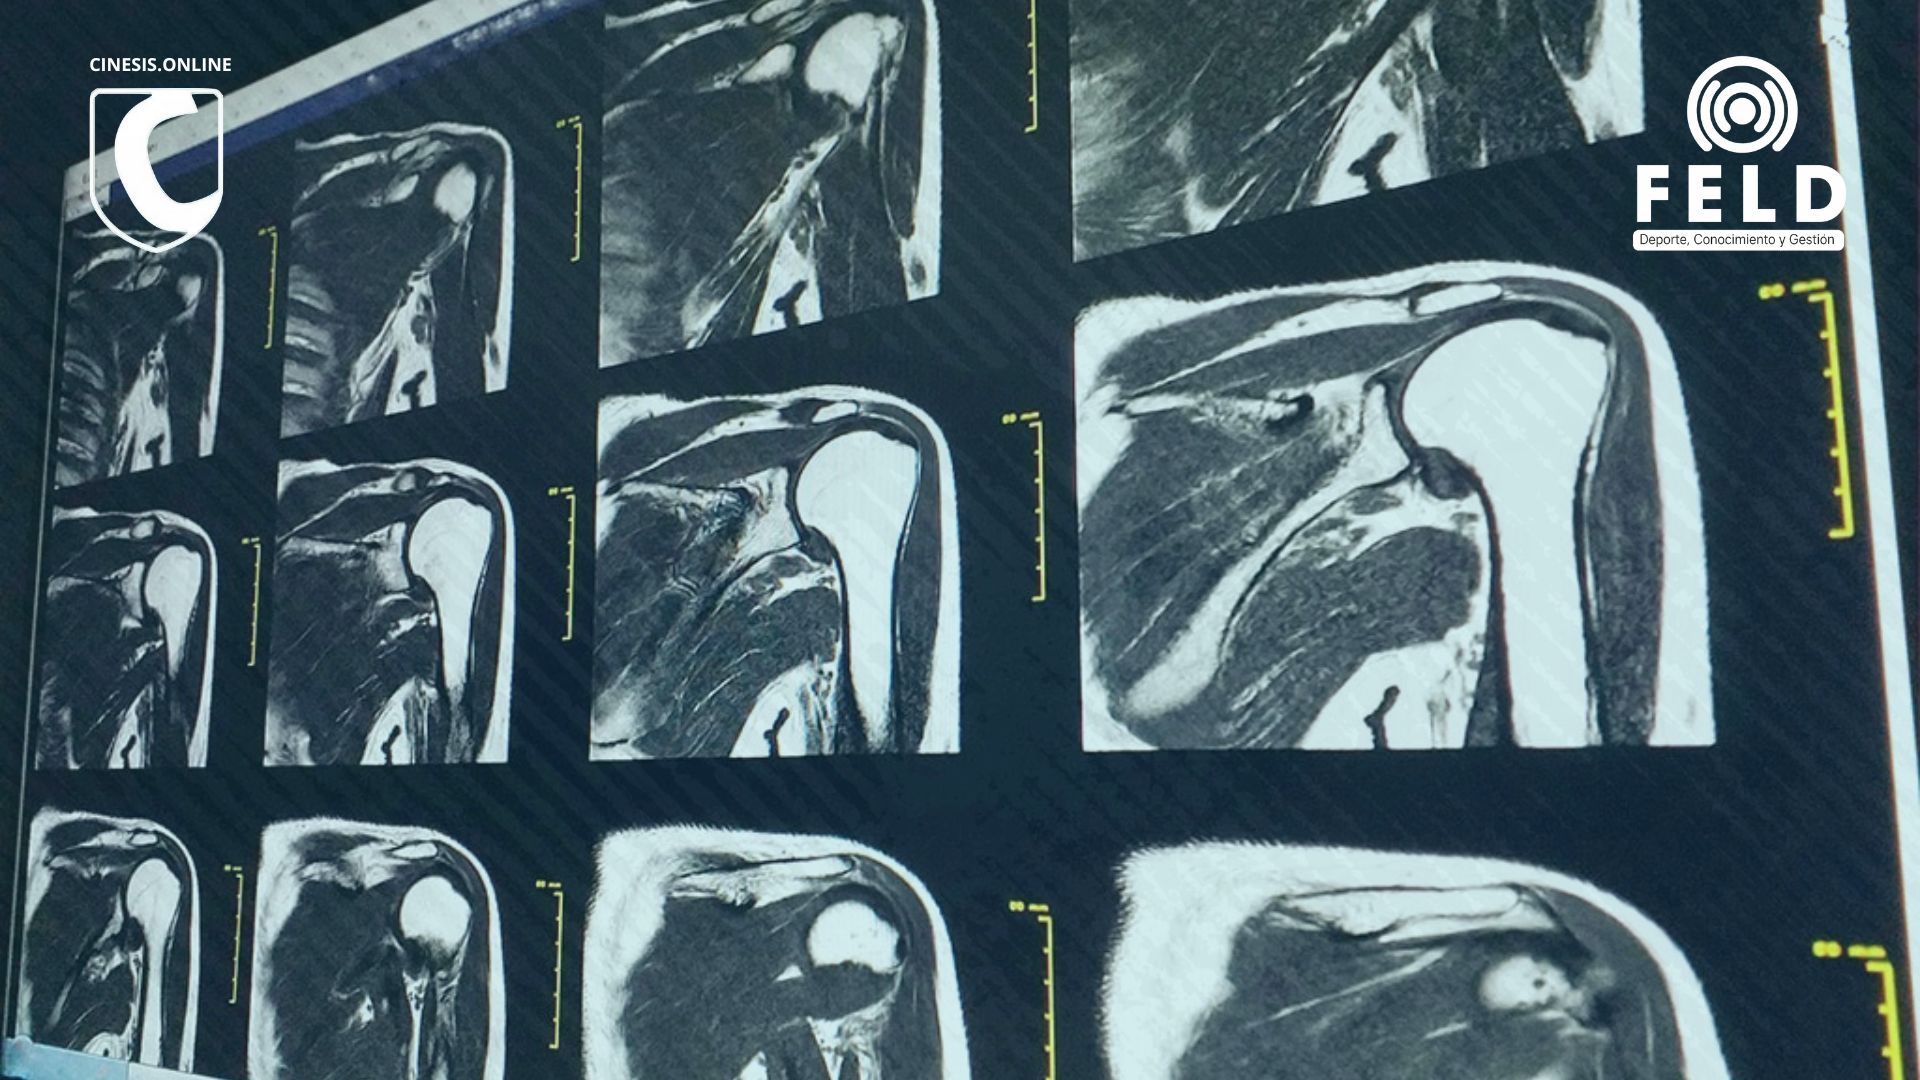

En la práctica diaria, el dolor de hombro es uno de los motivos de consulta más frecuentes (entre el segundo y el cuarto en Argentina, Policastro y cols. 2020). Y siempre aparece la misma pregunta: ¿los estudios de imagen son realmente necesarios?

Ahora bien, ¿qué pasa cuando la resonancia o la ecografía muestran “alteraciones” que también están presentes en personas sin dolor?

En 2019, Py Barreto y colegas publicaron un trabajo en el Journal of Shoulder and Elbow Surgery en el que evaluaron resonancias bilaterales en pacientes que tenían dolor en un solo hombro. El hallazgo fue contundente:

- La mayoría de las “lesiones” aparecían también en el hombro sano.

- Tendinopatías, cambios en la articulación acromioclavicular, líquido subacromial y lesiones labrales eran igual de frecuentes en hombros con dolor y sin dolor.

- Solo los desgarros completos del supraespinoso y la artrosis glenohumeral mostraron mayor prevalencia en los hombros sintomáticos… aunque otros estudios también describen estos hallazgos en personas sin síntomas.

En resumen: muchas veces la resonancia no explica el dolor del paciente.